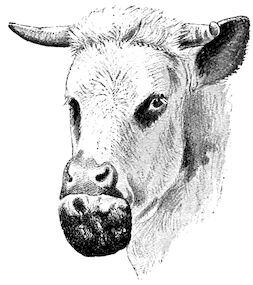

Fig. 4.—Deformity of the face in the horse shown in Fig. 2.

The flat bones are particularly liable to this change, which is common to domesticated animals. The bones of the head are the first to suffer; later those of the pelvis. The lower jaw becomes swollen, particularly about the centre of the branches which may attain three, four, or five times, their normal thickness.

The depression in the submaxillary space disappears. The upper jaw undergoes similar changes, becoming deformed and thickened until the cavities of the sinuses and the hollow appearance of the palate are lost, while the face is so changed that it cannot be recognised as that of a horse, goat, etc.

The molar teeth are almost buried, their tables alone being visible at the bottom of a depression, the edges of which rise above the neighbouring parts (pig).

Mastication is clearly impossible, the jaws appear paralysed, the muscles powerless, and only swallowing is possible, a fact which explains why life is only prolonged to this stage in animals which can be fed with a spoon or bottle (pigs and goats). The bones of the cranium, although greatly changed in texture, are always less deformed than those of the face.

The changes are such that it is often easy with a mere post-mortem knife to cut the head completely in two. Osseous tissue, properly so-called, has disappeared.

All the constituent tissues, with the exception of the skin and muscles, i.e., the bone, periosteum and aponeuroses, have the appearance and consistence on section of the fibro-lardaceous tissue seen in chronic inflammation.

Fig. 5.—Head of a pig suffering from osseous cachexia.

“The disease may advance for two or three months, and in case of pelvic fractures and distortions, there may be permanent lameness, and dangerous obstruction to parturition, even though the bones should acquire their normal hardness through the deposition of lime salts.”

Fig. 7.—Osseous cachexia: softening of the maxillæ.

Fig. 8.—Transverse section through the middle region of the face in a pig suffering from osseous cachexia.

18In the final stages, the bones may be cut with a knife, and a time arrives when bony tissue seems completely to have disappeared; thus, as shown in Fig. 8 herewith, it was possible to cut the entire head of a pig into thin slices without the slightest difficulty. All parts of the head had been affected by the softening change.

From the chemical point of view, the diminution in mineral salts and in phosphate of calcium has long been recognised, but the degree of this change varies according to the phase. In human beings the proportions have been estimated as follows: Normal bone, 50 to 80 per cent. of phosphate of calcium; bone in persons suffering from osteomalacia, 5 to 20 per cent. of phosphate of calcium. The changes in the ossein have not been carefully studied. We only know that histologically the ossein becomes fibrillar, and that chemically it no longer retains its normal composition.